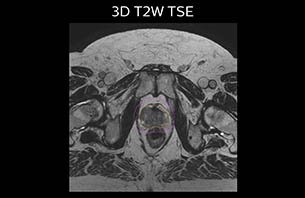

A 77-year-old male with prostate cancer cT3aN0M0, Gleason 8 and PSA 52 μg/L referred to androgen deprivation and radiation therapy with a prescribed dose of 50 Gy to the pelvic lymph node regions and 76 Gy to the prostate.

The 3D T1W FFE mDIXON sequence provides in-phase, water and fat images in one acquisition. Target and organs-at-risk are delineated on the 3D T2W TSE images. Prostate GTV is shown in orange, PTV in purple. The 3D bFFE sequence is used by the planner to mark the position of the fiducial markers (gold anchors) and contours are transferred to the digitally reconstructed radiographs (DRRs).